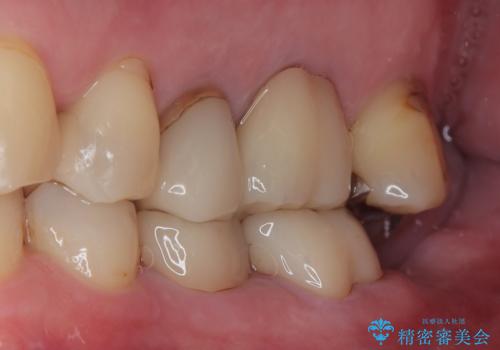

特に異常もなく見た目、噛み合わせともに満足していただけました。

ラバーダム防湿を行い、セラミックの接着をすることで、唾液や血液などの接着阻害因子を排除することができます。

歯と歯の間の虫歯をコンポジットレジンや保険のメタルインレーで治すと段差ができたりして清掃性が悪くなるので、セラミックインレー修復やゴールドインレー修復などの適合の良い詰め物で治療することをオススメします。